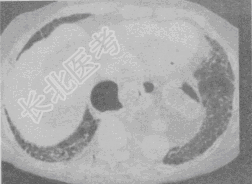

- 单项选择题患者,女, 45岁,气急, 咳嗽,胸痛, 手、足关节痛,关节肿胀, 结合CT图像,最可能的诊断是

A、肺癌

B、特发性肺间质纤维化

C、系统性红斑狼疮

D、硬皮病

E、类风湿肺病